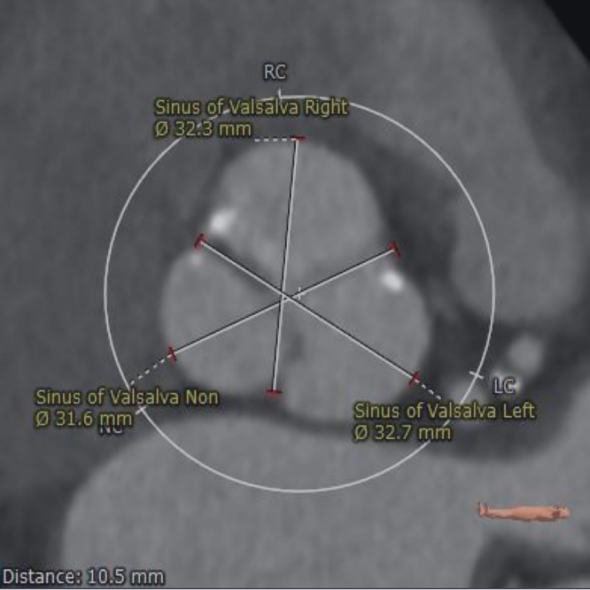

术前CT评估:

主动脉瓣瓣环周长69.8mm,平均周长径22.2mm。SOV:32.3mm*32.7mm*31.6mm,CT数据显示该患者为三叶式主动脉瓣,中度钙化,瓣叶增厚,钙化分布较均匀,主要分布于瓣叶边缘和管壁附着缘,瓣叶未见明显融合。

左冠开口高度15.3mm,右冠开口高度16.5mm,高度可,根据瓦氏窦内径和瓣叶长度综合判断,冠脉堵塞风险小。

主动脉根部测量:

冠脉高度测量: